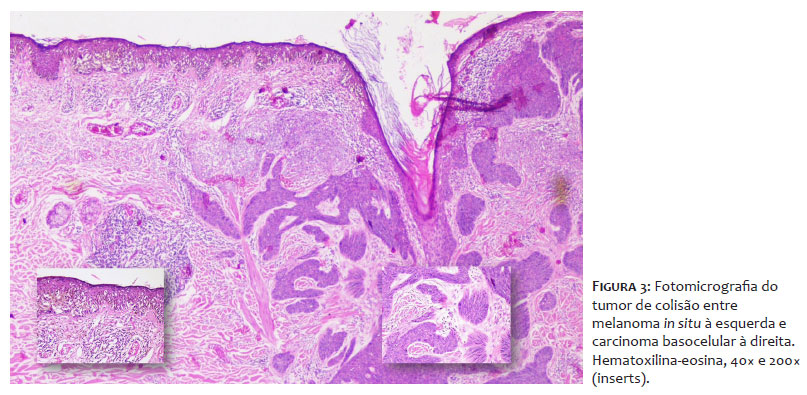

Foi realizada a ressecção da lesão, e o exame histopatológico confirmou o diagnóstico de tumor de colisão, composto por um melanoma in situ (à direita) e um CBC de padrão nodular (à esquerda). O melanoma apresentava nível de Clark I, ausência de ulceração, ausência de mitoses, embolização linfovascular e neurotropismo, infiltração linfocitária moderada, regressão tumoral presente e inferior a 75%, ausência de microssatelitose e margens laterais e profunda livres (Figura 3). A neoplasia melanocítica era composta por células isoladas e ninhos de células epitelioides atípicas, com disseminação pagetoide multifocal e abundante pigmentação. Na derme subjacente, observou-se derrame pigmentar, infiltrado linfocitário moderado e sinais de dano actínico severo. O CBC apresentava padrão nodular, sólido e adenoide, com áreas infiltrativas e pigmentação focal; ulceração; acometimento até a derme reticular média; ausência de infiltração perineural; e margens laterais e profundas livres.